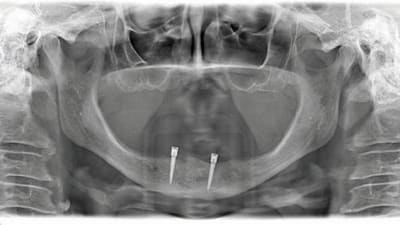

Step-by-Step Using Collaboration and Technology to Deliver By Victor Castro, CDT, Wesam Salha, DDS May 01, 2019 3 min read